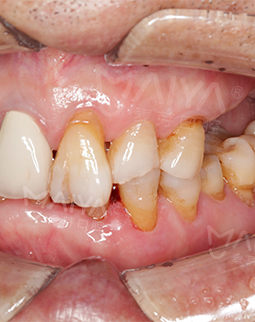

2018年5月28日 麦芽微创无痛种植牙 种牙全程无痛感

孙博人很亲切,一直在和我沟通,让我知道进行到哪一步了,也就1小时左右吧,医护人员就扶我坐起来,说手术做完了,确实没什么疼痛感。我要提醒缺牙的朋友,及早修补,避免剩余好牙脱落,影响健康!